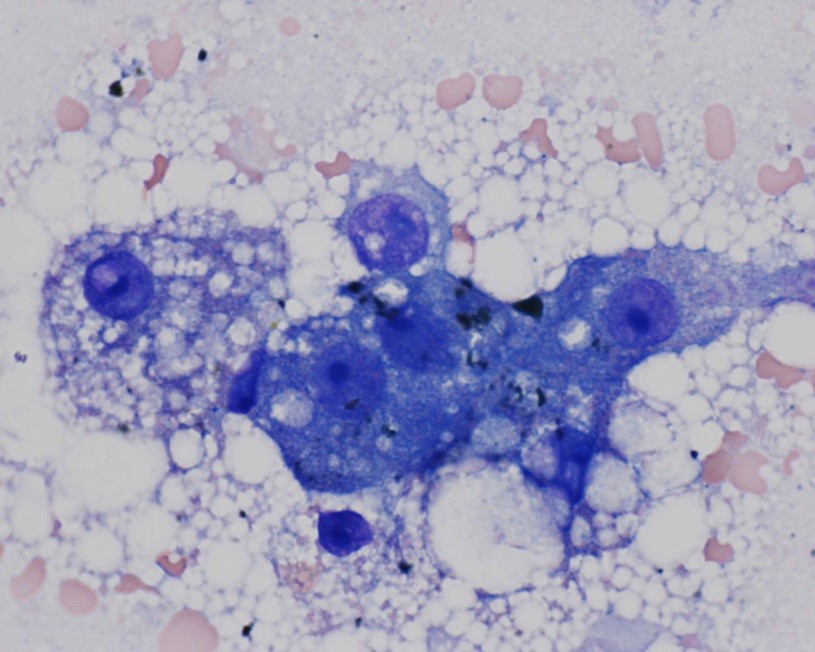

Cytology of fine-needle liver biopsy: Highly cellular sample contains hepatocytes with marked vacuolation and extracellular bile casts.

High Power view